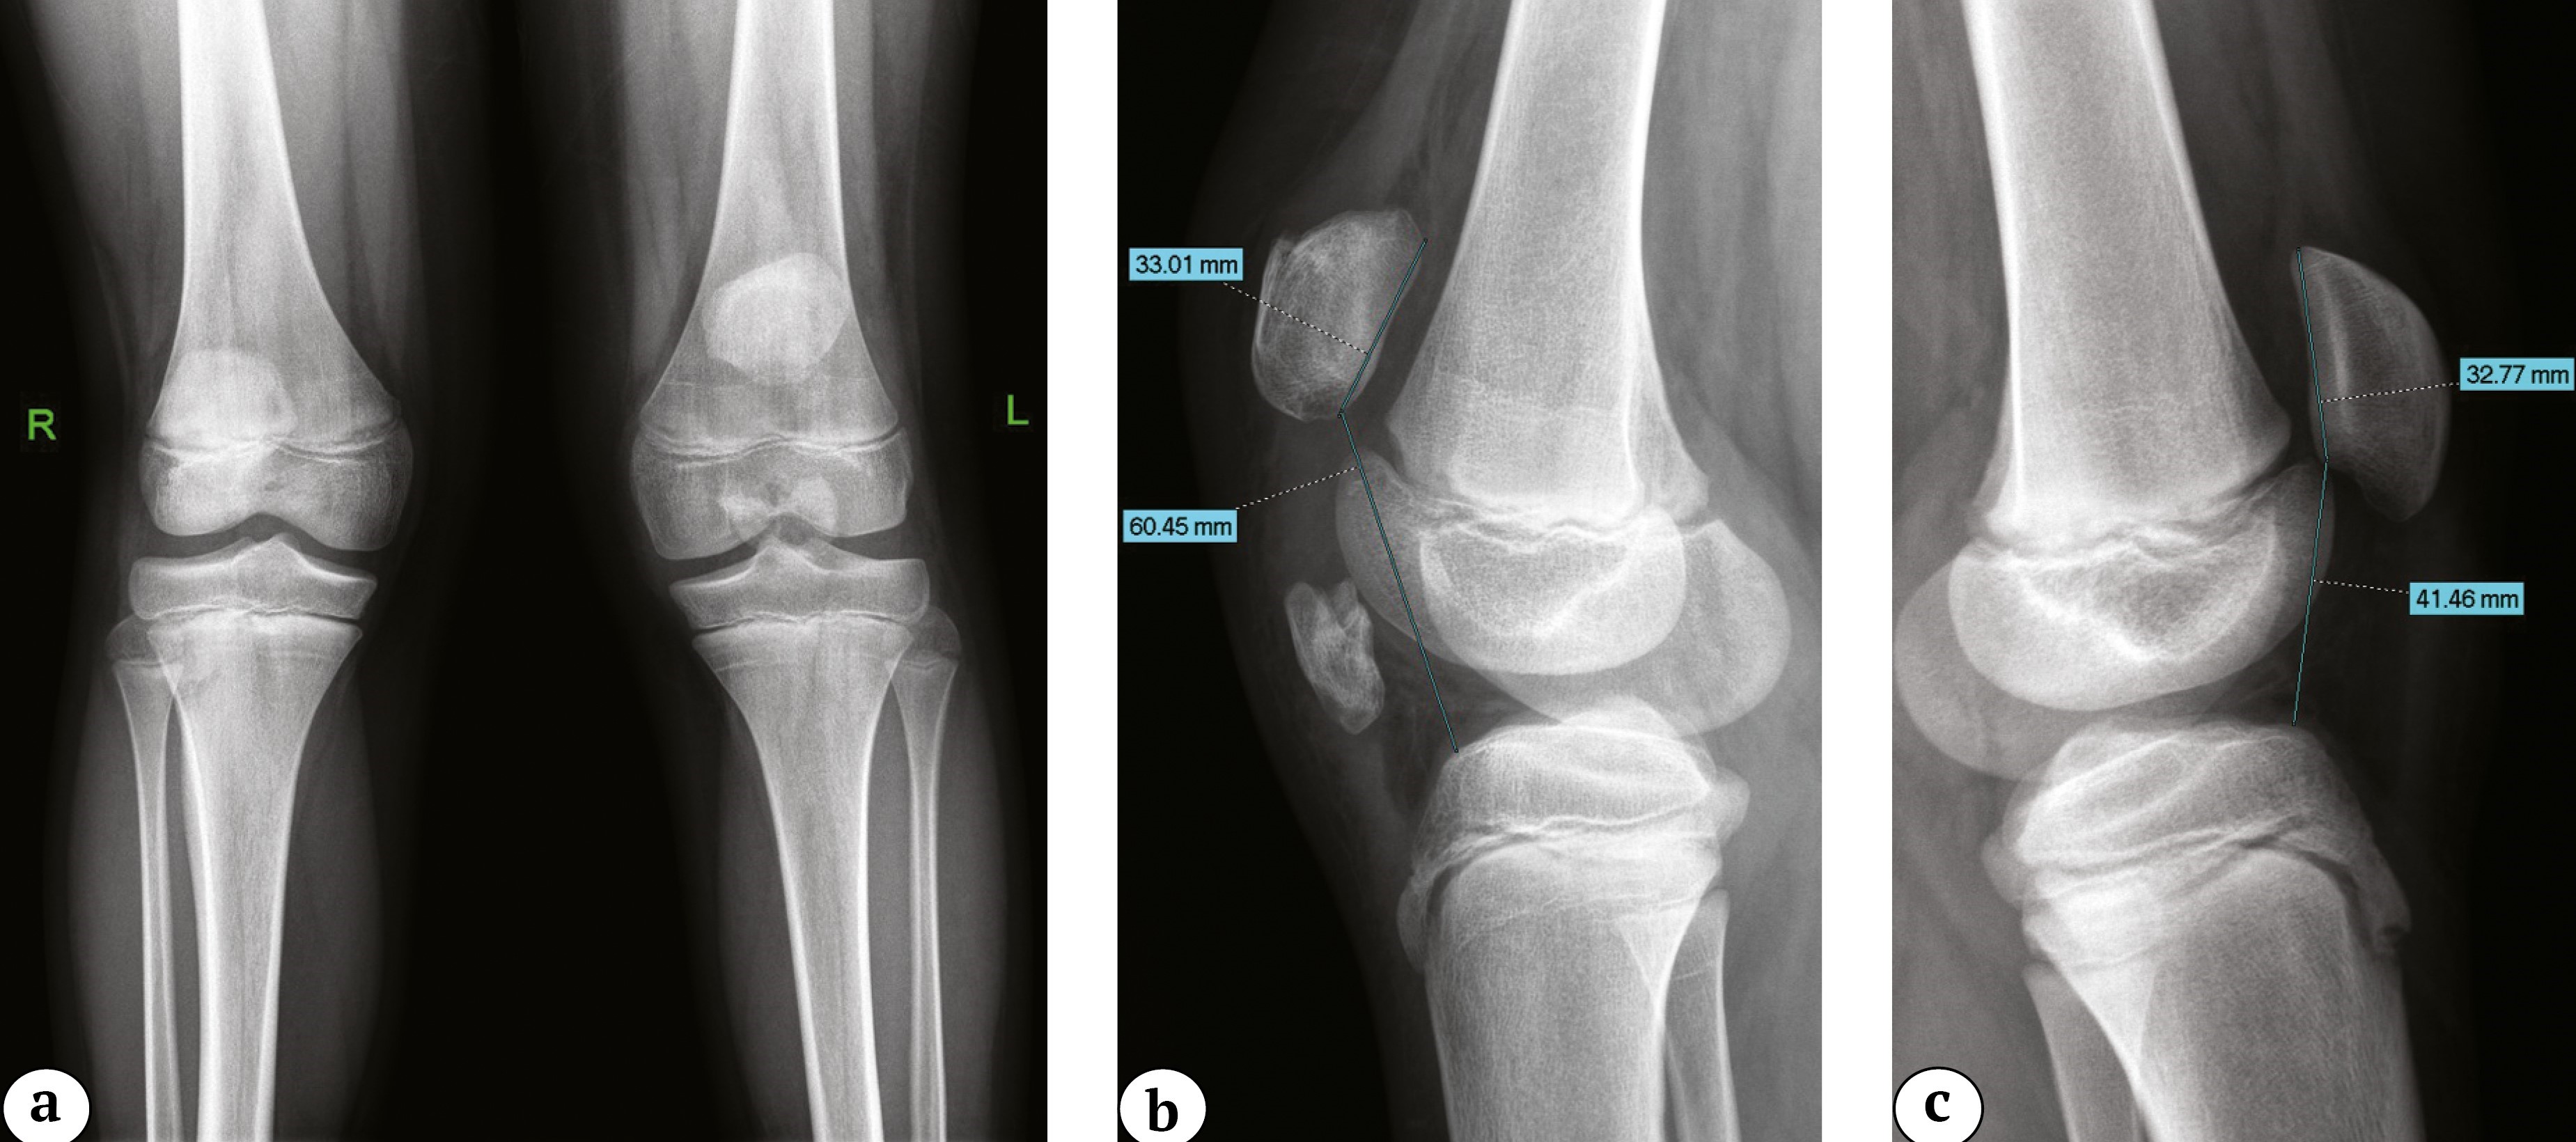

Лучевая картина. На рентгенограммах коленного сустава, выполненных в двух проекциях, у всех пациентов в проекции связки определялись костной плотности образования с неровным четким контуром в сочетании с высоким стоянием надколенника в прямой и боковой проекциях с увеличением индекса Caton – Deschamp (CDI) более 1,3 (рис. 1). Характеристика визуализируемых образований представлена в таблице 2.

Рис. 1. Рентгенограммы коленных суставов с односторонней оссификацией связки надколенника: а — прямая проекция, patella alta, оссификаты в проекции связки надколенника; b — боковая проекция, травмированная конечность, patella alta (индекс Caton – Deschamp — 1,8), оссификат в проекции толщи связки надколенника; c — боковая проекция, здоровая конечность

Figure 1. X-rays of the knee joints with unilateral patellar tendon ossification: a — AP view, patella alta, ossifications in the projection of the patellar tendon; b — lateral view, an injured limb, patella alta (Caton-Deschamps index — 1.8), ossification in the projection of the patellar tendon thickness; c — lateral view, a healthy limb